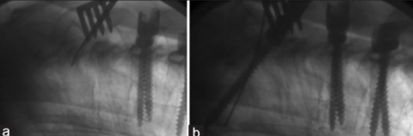

(1)横突钩和移行棒

图28-29 据文献报道,对于UIV应用横突钩和移行棒可以一定程度避免PJK/PJF的发生